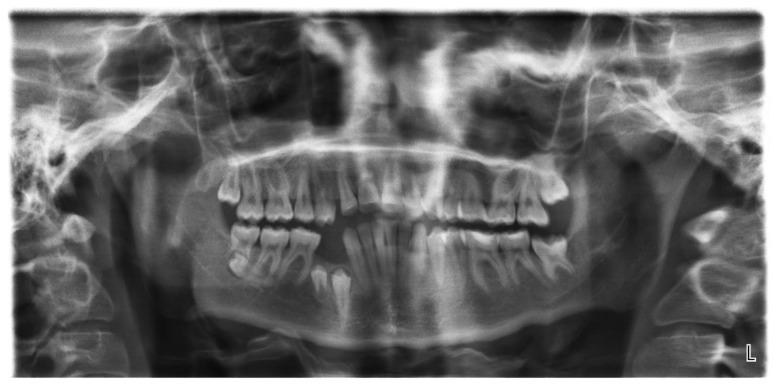

We described an 11-year follow-up of a patient with a non-syndrome multiple supernumerary teeth who had one extra tooth in the maxilla and four additional premolars in the mandible. Together with an additional distal migration of the second lower right premolar to the ramus of the mandible that also occurred, it comprises a unique combination of conditions that were not previously presented in the literature. We showed the significance of routine X-rays in cases of hyperdontia since the additional teeth may develop later than expected and the patient may not experience any symptoms.

我们描述了一例非综合征性多生牙患者的11年随访情况,该患者上颌有一颗额外牙齿,下颌有四颗额外的前磨牙。再加上右下第二前磨牙向下颌升支的额外远中移位,这构成了一种文献中未曾报道过的独特情况组合。我们展示了在多生牙病例中进行常规X线检查的重要性,因为额外的牙齿可能比预期发育得晚,且患者可能没有任何症状。